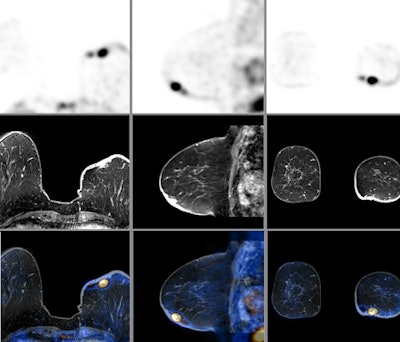

![]() |

| PET, MR, and fused PET/MR images of a breast cancer patient. Images courtesy of the University of Geneva. |

Philips believes that PET/MRI will demonstrate its value in a number of clinical applications, including areas such as the prostate and breast, which have been more difficult to image with PET/CT. PET/MRI scans are performed with the company's time-of-flight protocols, and MR images are used for attenuation correction as well.